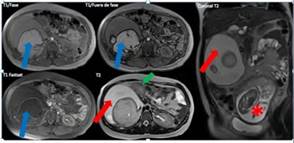

Paciente de 19 años, con embarazo de 19 semanas, quien consultó en febrero del año 2017 al servicio de urgencias de la Clínica Universitaria Colombia, institución de alta complejidad ubicada en Bogotá, que atiende pacientes afiliados al régimen contributivo en el Sistema General de Seguridad Social en Colombia. Consultó por primer episodio de dolor en epigastrio tipo peso, intensidad 4/10, de 10 días de evolución, acompañado de emesis con contenido gástrico; no presentaba antecedentes personales patológicos, farmacológicos ni quirúrgicos; antecedentes ginecológicos, con menarquia a los 15 años, periodos menstruales regulares, primigestante de un embarazo deseado, con asistencia a tres con- troles prenatales. El examen físico arrojó tensión arterial de 110/60 mm/Hg, frecuencia cardiaca de 80 latidos por minuto (l/m), frecuencia respiratoria de 16 respiraciones minuto, escala de Glaslow de 15/15 y temperatura de 36 grados centígrados, con mucosa oral seca, presentaba dolor a la palpación en epigastrio e hipocondrio derecho sin irritación peritoneal, altura uterina de 18 centímetros con feto único longitudinal y fetocardia de 148 l/m, exploración ginecológica sin pérdidas vaginales por lo cual no se realizó examen ginecológico. Con diagnóstico de dolor abdominal en estudio, deshidratación y sospecha de colelitiasis se hospitalizó para inicio de cristaloides parenterales y toma de estudios complementarios. El laboratorio mostró hemograma sin leucocitosis, con un diferencial leucocitario normal; las funciones hepática y renal normales, parcial de orina normal. Se realizó ecografía obstétrica con una biometría para 19 semanas, peso fetal estimado de 264 g, percentil 52 %, placenta normo-inserta, índice de líquido amniótico de 13,5 cm. Para excluir colelitiasis se tomó ultrasonido abdominal que descartó patología biliar y evidenció un tumor sólido de contornos regulares, retroperitoneal derecho, de 15 x 13 x 13 cm, con ecogenicidad heterogénea por probable componente graso, y material ecogénico que proyecta sombra acústica por probable componente óseo (figura1); el estudio se complementó con resonancia magnética, la cual mostró un tumor retroperitoneal de 20 x 13 x 15 cm, encapsulado, con bordes definidos, áreas hiperintensas en secuencia T1, hipointensas en secuencias FatSat por contenido graso; y otras áreas hipointensas en T1 e hiperintensas en T2 por componente quístico tumoral; en el interior del componente graso se hallaron múltiples áreas marcadamente hipointensas que corresponden a tejido de tipo cálcico. Respecto a la glándula suprarrenal derecha, se encontró que ejercía efecto compresivo, desplazando asas intestinales y riñón sin invasión de dichas estructuras. Como posibles diagnósticos se consideraron: teratoma maligno frente a liposarcoma (figura 2). Ante el diagnóstico de tumor retroperitoneal de naturaleza desconocida se solicitó marcador tumoral antígeno del cáncer 125 (CA-125) de 15,7 U/mL, con valor de referencia normal menor a 35 U/mL. Se realizó por parte de radiología intervencionista una biopsia percutánea guiada por ecografía con aguja Tru-cut, se obtuvieron dos cilindros de muestra del componente sólido del tumor, sin complicaciones. En el segundo día de hospitalización la paciente presentó mejoría con resolución del dolor abdominal al manejo con metamizol parenteral, y con tolerancia de la vía oral se dio salida hospitalaria.